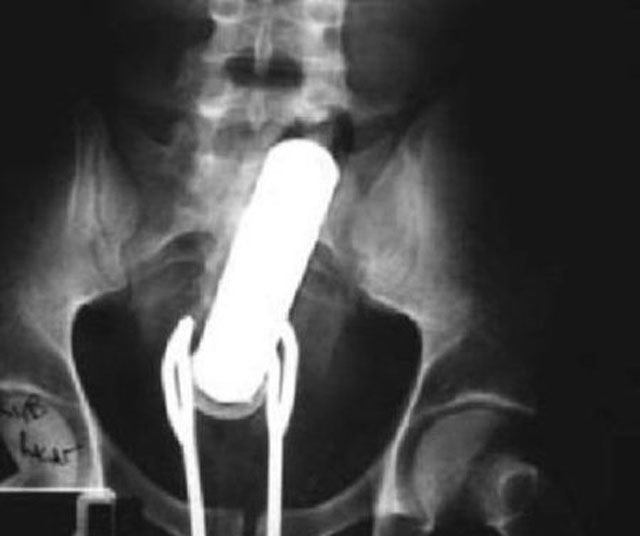

A new hip didn't slow this person down